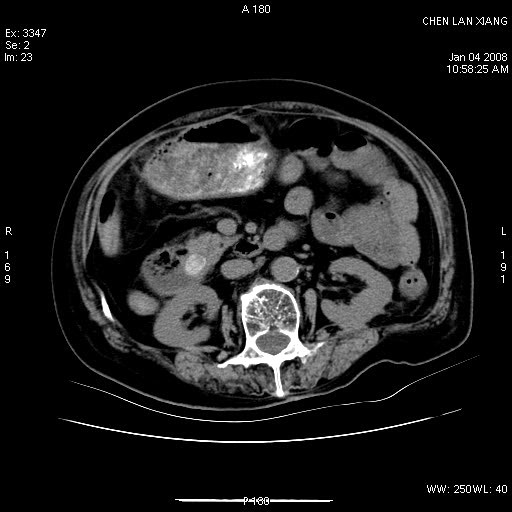

女,76岁,腹痛3-4天,b超示:肝内实性肿物,胆囊强回声,胆总管扩张.

考虑:1、胆总管下端结石伴梗阻性肝内外胆管扩张(肝左叶外侧段肝内胆管多发结石、胆管炎);

胆囊内结增强影,肝内胆管、胆总管扩张明显。肝内胆管、胆总管下段多发结石,胆囊癌,建议mrcp检查

胆囊密度增高,增强后周边肝组织及胆囊窝下部周边软组织延时性不规则强化.然胆囊壁未见明显不规则增厚及肿块.左侧肝内胆管及胆总管下段结石伴胆系扩张.

考虑;胆囊炎(黄色肉芽肿性胆囊炎?),左侧肝内胆管及胆总管下段结石.

ct所见:1、 肝内胆管结石,肝内外胆管扩张。低位胆道梗阻,胆总管下端结石;2 胆囊扩大,胆囊壁不规则增厚

考虑:胆总管下端结石并肝内外胆管扩张,肝内胆管结石;

1)胆囊癌伴肝脏转移。2)胆总管下端结石、肝内胆管结石伴肝内外胆管扩张。